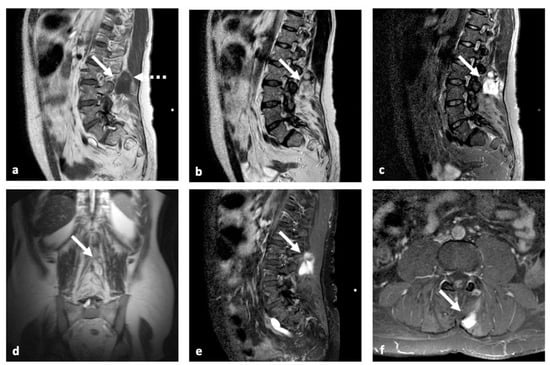

| MRI | Nonspecific: low SI on T1w; high SI on T2w; variable C.E. | Identical to fat; no C.E. | Adipose areas; non adipose areas: low SI on T1w, high SI on T2w, variable C.E. | Nonspecific: intermediate SI on both T1w and T2w | Low to intermediate SI on T1w; high SI on T2w; a small rim of fat and edema in adjacent muscles; variable C.E. |